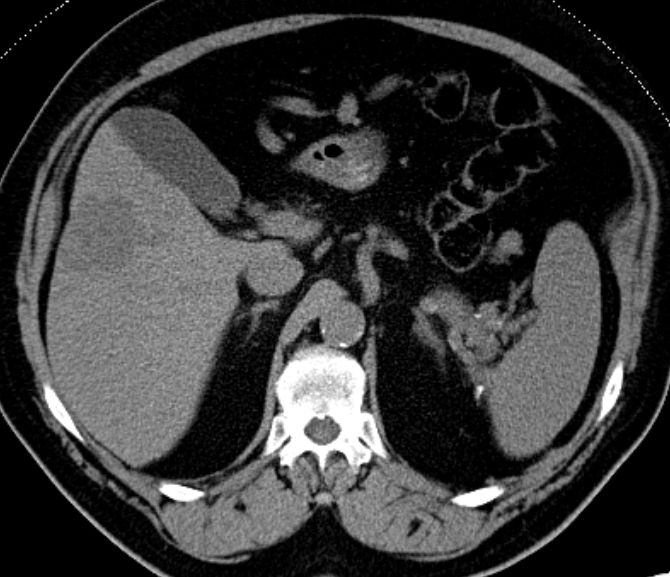

75-jähriger Mann mit Herdbefund in der Leber. Nach Kontrastmittel ist der Herd in der arteriellen Phase hypodens. ![]() | |